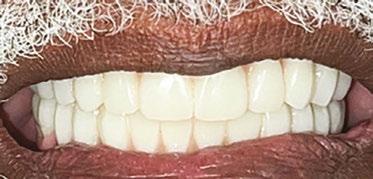

5 and 6). and Douglas D. Wright, DDS, is a general dentist in private practice in Staunton, Virginia. William T. Goodwin II, DDS, is a maxillofacial surgeon in private practice in Harrisonburg, Virginia. For questions about this article, please contact Dr. Wright at dominosign14@ gmail.com. Figure 1: Pretreatment photo of patient. Note the extreme wear of mandibular incisors occurring from uncorrected malocclusion. Also note the contact between tooth Nos. 9 and 22 when the mandible moves to the right. This “canine guidance” was incorporated into the fixed-bridge design on the patient’s upper right side Figures 2 and 3: Metal framework at try-in appointment. Porcelain-fused-tometal was used to restore this case because of lack of interarch space

Retaining tooth No. 6 and placing the dental implant through the impacted and ankylosed tooth provided a new set of challenges. Keeping the ankylosed canine in place reduced the need for additional surgery; however, with the retention of the canine, insufficient interarch space would be available for a zirconia or resin-composite restoration. Because the interarch space was limited, a porcelainfused-to-metal restoration was used to complete the case.

To prevent isolated forces being placed on the new implantretained fixed bridge, modified anterior and “canine” guidance

was achieved by allowing the already established guidance between tooth Nos. 9 and 22 when the mandible moved to the patient’s right. The new bridge had occlusal forces balanced to the guidance provided by the contact in function between tooth Nos. 9 and 22 (Figure 1).

Restorative dentists often come up against multiple restorative challenges in a single patient. There are few reports of treating cases such as this with multiple challenges. Each individual restorative challenge can be reviewed in dental literature. Creative solutions can be offered to the patient based on clinical research, case reports, and well-established clinical practices (Figures 2, 3, 7, and 8).